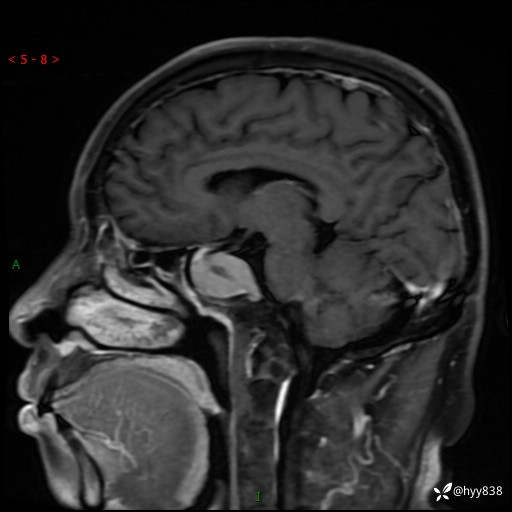

MRI增强(外院平扫)